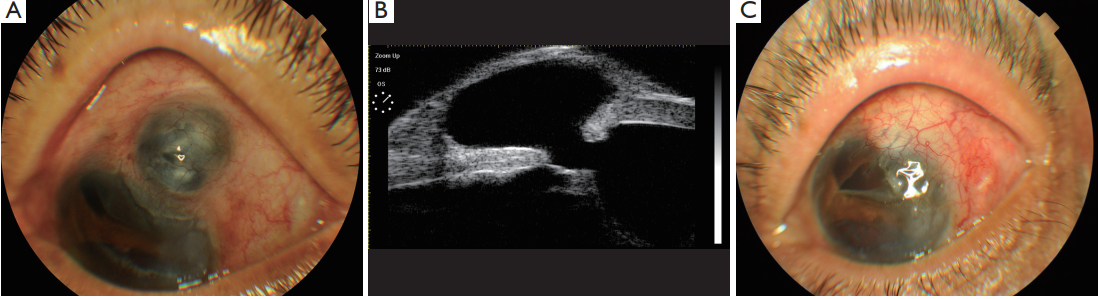

Case 1 (Figure 1): a 3-year-old young girl was referred to our hospital with a history of congenital corneal dermoid resection without graft one year ago. She complained of foreign body sensation and “black lump” on the operated eye postoperatively. No other history was reported. Best-corrected visual acuity (BCVA) was 4/20 in the left eye and intraocular pressure (IOP) was 15 mmHg. Slit-lamp examination revealed a 6 mm × 7 mm brown protruding bulge on the infratemporal. The anterior chamber and fundus examination showed no abnormal. BCVA was 12/20 and slit-lamp examination showed no obvious abnormalities in the right eye. Laboratory examinations results were normal, including blood-R, urine-R, blood biochemistry, hemostatic, HIV, HCV, HBSAg, RPR, chest X-ray, electrocardiogram and other immune inspections. The diagnosis of Scleral staphyloma was given and an operation of Sclera patch graft was performed. In the period of 30 months following-up, the BCVA was 10/20 and the foreign body sensation disappeared in the left eye. Slit-lamp examination revealed no scleral rejection and conjunctival dissolution.

Figure 1 Scleral staphyloma after corneal dermoid resection. (A) Pre-op; (B) UBM pre-op; (C) post-op. UBM, ultrasound biomicroscopy.